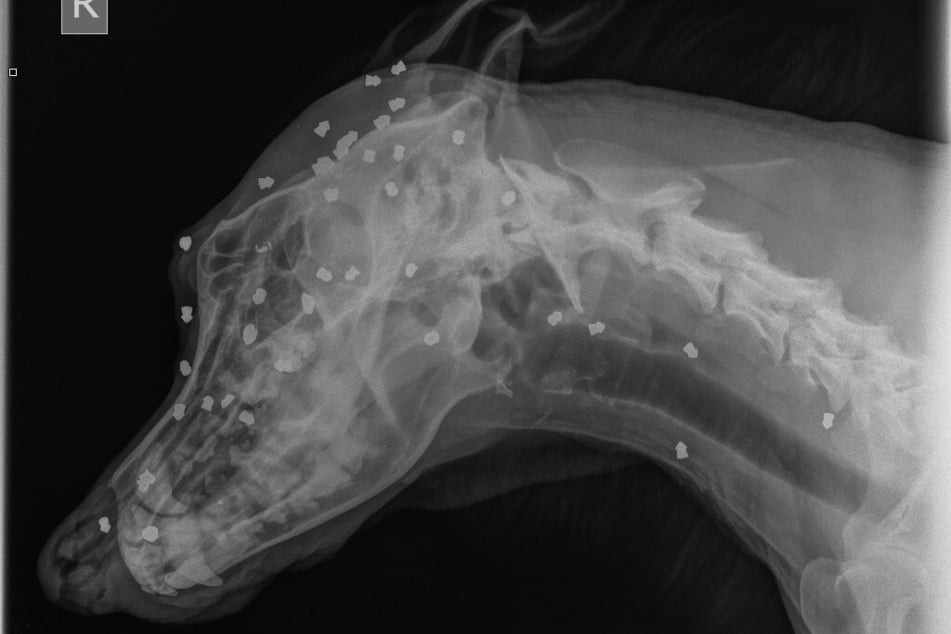

Bautzen - Noch immer gilt es als ein Wunder: Schäferhund-Mischling Keks hatte 42 Geschosse im Körper stecken, viele davon im Kopf - und überlebte. Am Montag nun verurteilte das Amtsgericht Bautzen sein ehemaliges Herrchen zu 110 Tagessätzen à 15 Euro. Er hatte das Tier über Wochen hinweg gequält.

Ihm geht's gut und er hat das Vertrauen in die Menschheit wohl noch nicht verloren: "Der liebt Menschen trotz allem", sagt Maria Göpfert (38), stellvertretende Tierheimleiterin in Bloaschütz, die den Vierbeiner am 28. April gleich selbst adoptiert hatte. Sie hatte auch ein Diabolo in einer Wunde entdeckt, was nach dem Röntgen dann die Ermittlungen in Gang setzte.

Im Tierheim fielen die Wunden, die Andreas L. nie bemerkt haben will, sofort auf. Nur dachten die Mitarbeiter da noch nicht an Schusswunden. "Es ist relativ selten, eigentlich hatte ich das noch gar nicht, dass jemand seinen eigenen Hund so derart quält", sagte der Staatsanwalt.